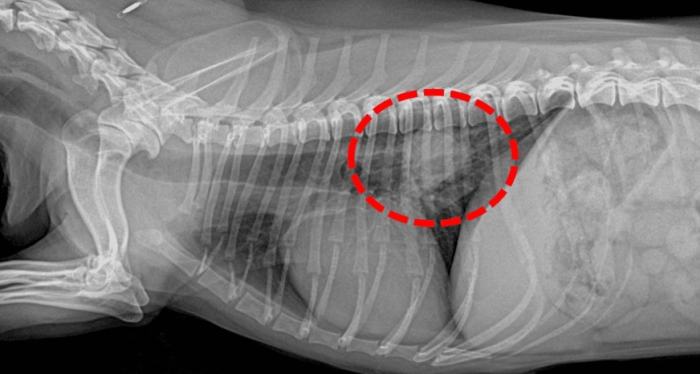

診斷過程通常需要多管齊下。獸醫可能會先聽診,然後建議做X光或超音波。X光是最基本的工具,可以看肺部的陰影變化。但如果腫瘤很小,X光可能看不出來,這時就需要進階檢查如CT掃描。

| 影像學檢查 | X光、超音波 | 查看肺部有無異常陰影 |